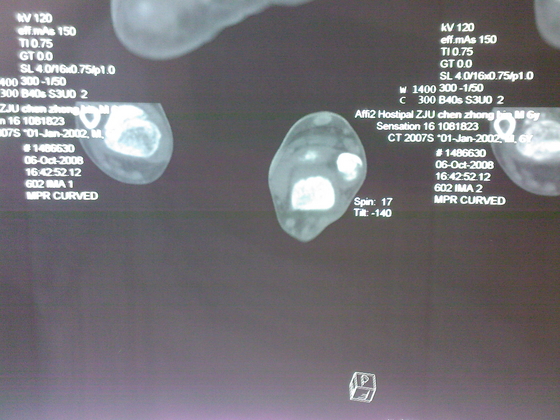

把病理送浙一医会诊后诊断为:骨外软骨瘤。同时做了CT检查。暂未予治疗。

今天把创面情况跟CT发上请大家看看。

继续发CT片